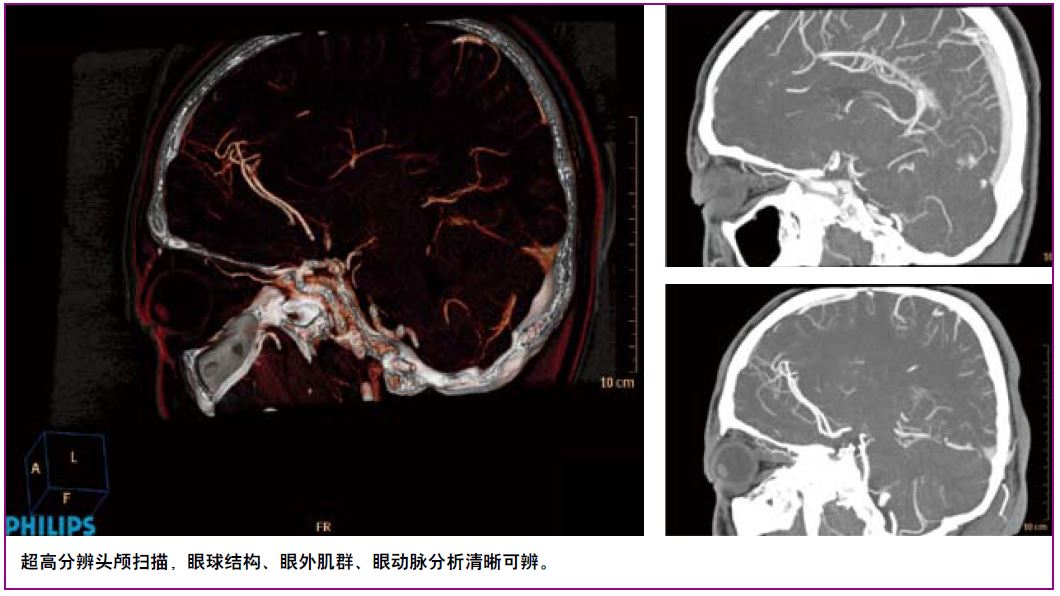

Brilliance ICT临床应用展示

纤毫毕现

显微成像——动态四焦点及纳米探测器实现4800采样/0.27秒最高采样率,丰富信息成就1024x1024超高分辨成像技术,4倍信息量提升令微小病灶诊断不再困惑。同时高效的祛金属伪影O-Mar功能防止漏诊情况。

全景成像——基于宽体探测器及极速扫描实现无扫描范围限制、超低辐射剂量的高清动态全景成像,一次扫描,解剖细节及生理动态同时呈现。